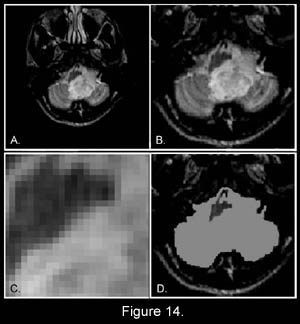

Figure 14 is an axial (cross-sectional) image of the brain showing a tumor of the cerebellum (white areas) in the midline. Figure 14c is a magnified image showing the picture elements or "pixels" (small squares) that make up the image. The cerebellar tumor as it would appear (D) with no MR signal differences. Figure D is the same image as B but where all MR signal differences were eliminated and all the MR pixels therefore had the same pixel brightness. The absence of the MR signal differences between cancer and normal tissue discovered by Damadian gives the MR image pixels equal brightness and the tumor becomes Invisible. |

Were the amplitudes of the NMR signals (fig.9) used to set the brightness of each MRI image pixel the same for all tissues (and prior to Dr. Damadian's discovery such NMR tissue signal differences were not known to exist) the brightness of each image pixel would be the same. The MR image would be a blank.

(difference in pixel brightness of adjacent image pixels) A typical

medical image is constructed from PICTURE

ELEMENTS designated PIXELS

(Fig 14C) in medical imaging nomenclature.

Fig. 14 A typical

256 X 256 medical image therefore is a composite of

65,536 picture elements

(pixels-Fig 14c) Accordingly the power to visualize DETAIL in the body's CRITICAL SOFT TISSUE VITAL ORGANS (e.g. Brain, Heart, Muscles, Kidney, Liver, Spleen, Pancreas, Intestines) therefore RESTS ENTIRELY on the power of the imaging technology to generate the PIXEL CONTRAST needed to visualize IMAGE DETAIL in the body's vital tissues. The existing x-ray technology for visualizing IMAGE DETAIL in the body's CRITICAL VITAL ORGANS had been severely lacking in its power to generate the PIXEL CONTRAST needed to visualize IMAGE DETAIL in the body's CRITICAL VITAL SOFT-TISSUE ORGANS Dr. Damadian's

The power to visualize detail in any pixel image resides

in the power of the individual image pixel to generate

differences in pixel brightness (PIXEL

CONTRAST)

(Fig 14a, b, c, d)